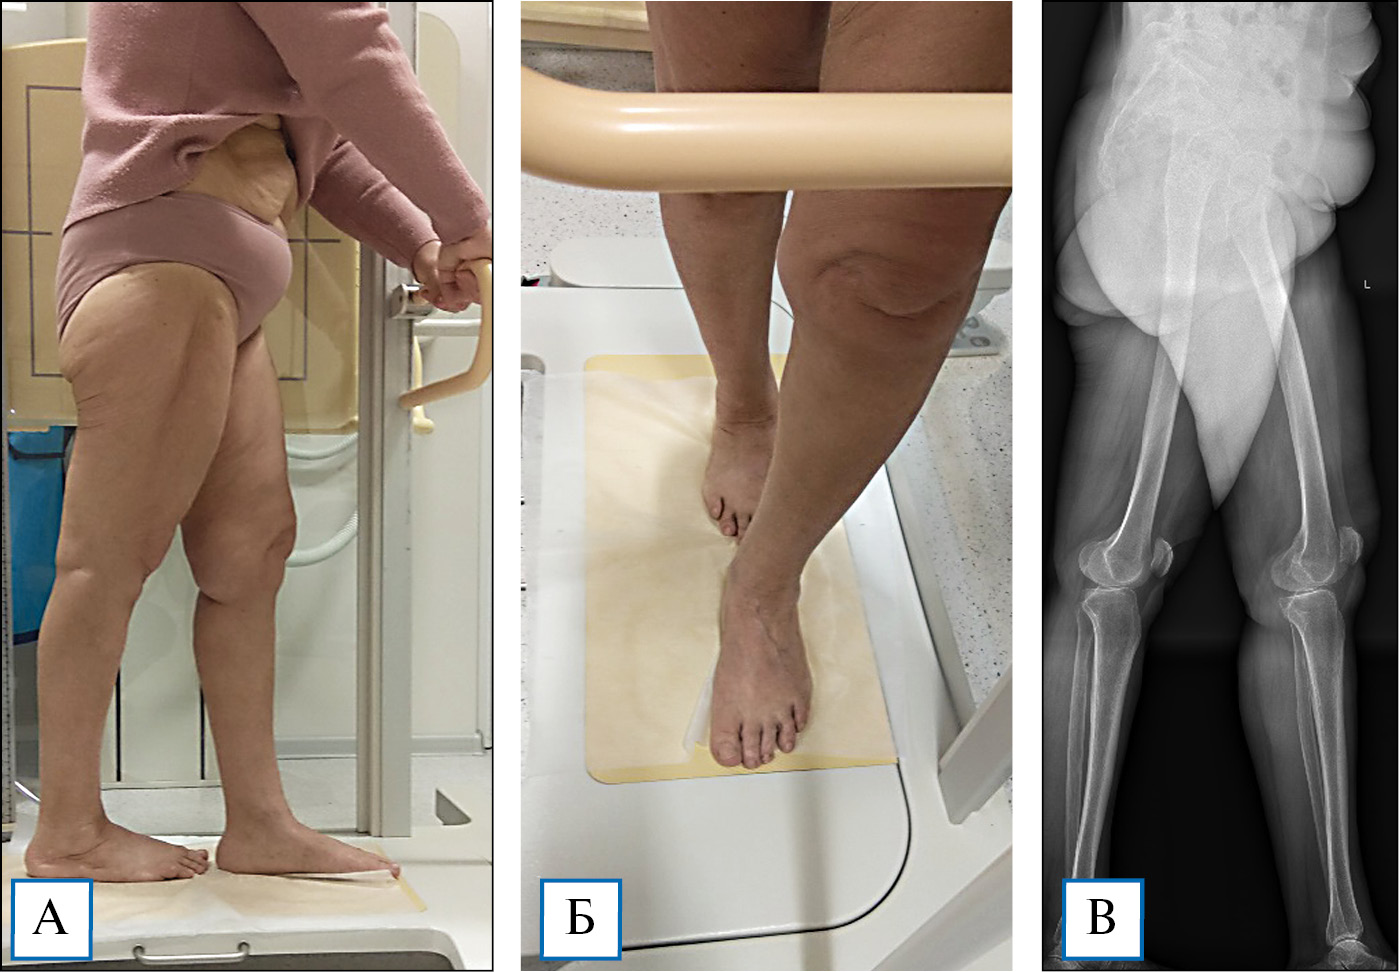

Технология внешнего остеосинтеза по Илизарову обеспечивает точную коррекцию в соответствии с запланированными параметрами (рис. 3, 4).

Рис. 3. Пациентка в возрасте 57 лет с двусторонней варусной деформацией и гонартрозом II стадии

Примечание. А — до операции; Б — в процессе коррекции; В — по завершении лечения.

Рис. 4. Рентгенограммы той же пациентки с двусторонней варусной деформацией и гонартрозом II стадии: точная симметричная коррекция формы нижних конечностей с перемещением механической оси в нормальное (нейтральное) положение

Примечание. А — до операции; Б — по завершении лечения; В — в процессе коррекции (через 2 мес после операции).